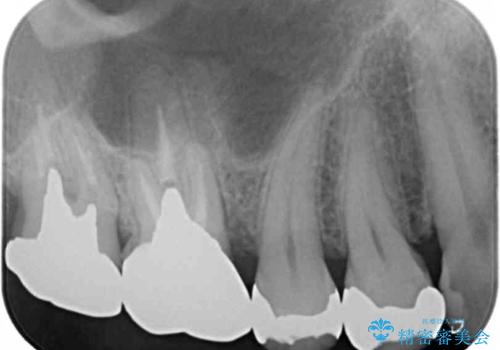

- 笑った時にチラつく銀歯が気になるから白くしたいとのことで来院。

銀の詰め物を除去し、残った歯の量が多かったためセラミックインレーでの修復となりました。

また今回は治療前の写真で食べ物が詰まっている様子が伺えますが、適合がよく段差のない修復をすることで食べ物が詰まることを減らし、結果的に虫歯のリスクを下げることも期待できます。